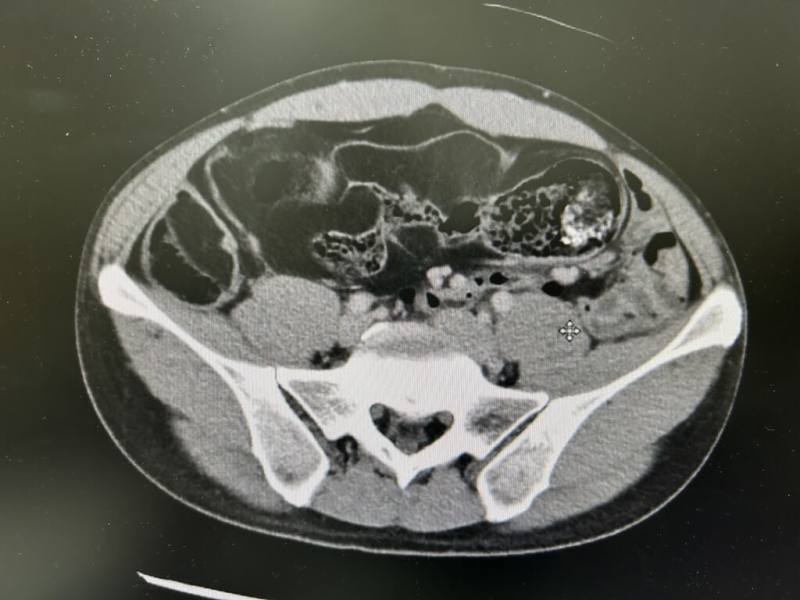

經過電腦斷層掃描,發現腹腔內多處低回音腫塊,並合併嚴重腸道糞便滯留,醫療團隊初步懷疑為「惡性腹腔脂肪肉瘤」,經多專科團隊會診後,決定採剖腹探查。不料手術驚見患者末端小腸嚴重糾結,腸腔內填滿脂肪樣腫瘤與軟便,並合併無數大小不一的腸憩室。